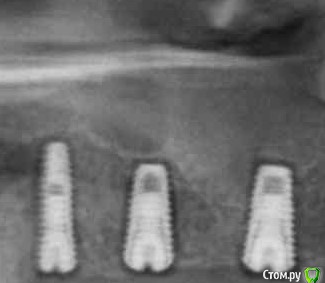

#недозаглубили ....или плюсом десны маловато,вот и при формировании биоширины кость ушла

да нееееет )))) тут как раз наоборот, хирург все норм сделал, а кость ушла от неправильных абатментов.

тот самый случай, когда абатмент с короткой шейкой убил хорошую хирургическую работу